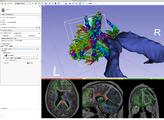

Fetal brain development. The visualization is using volume rendering and the Multivolume modules in Slicer 4. Click here for the full movie (~24mb). Data downloaded from Imperial College.